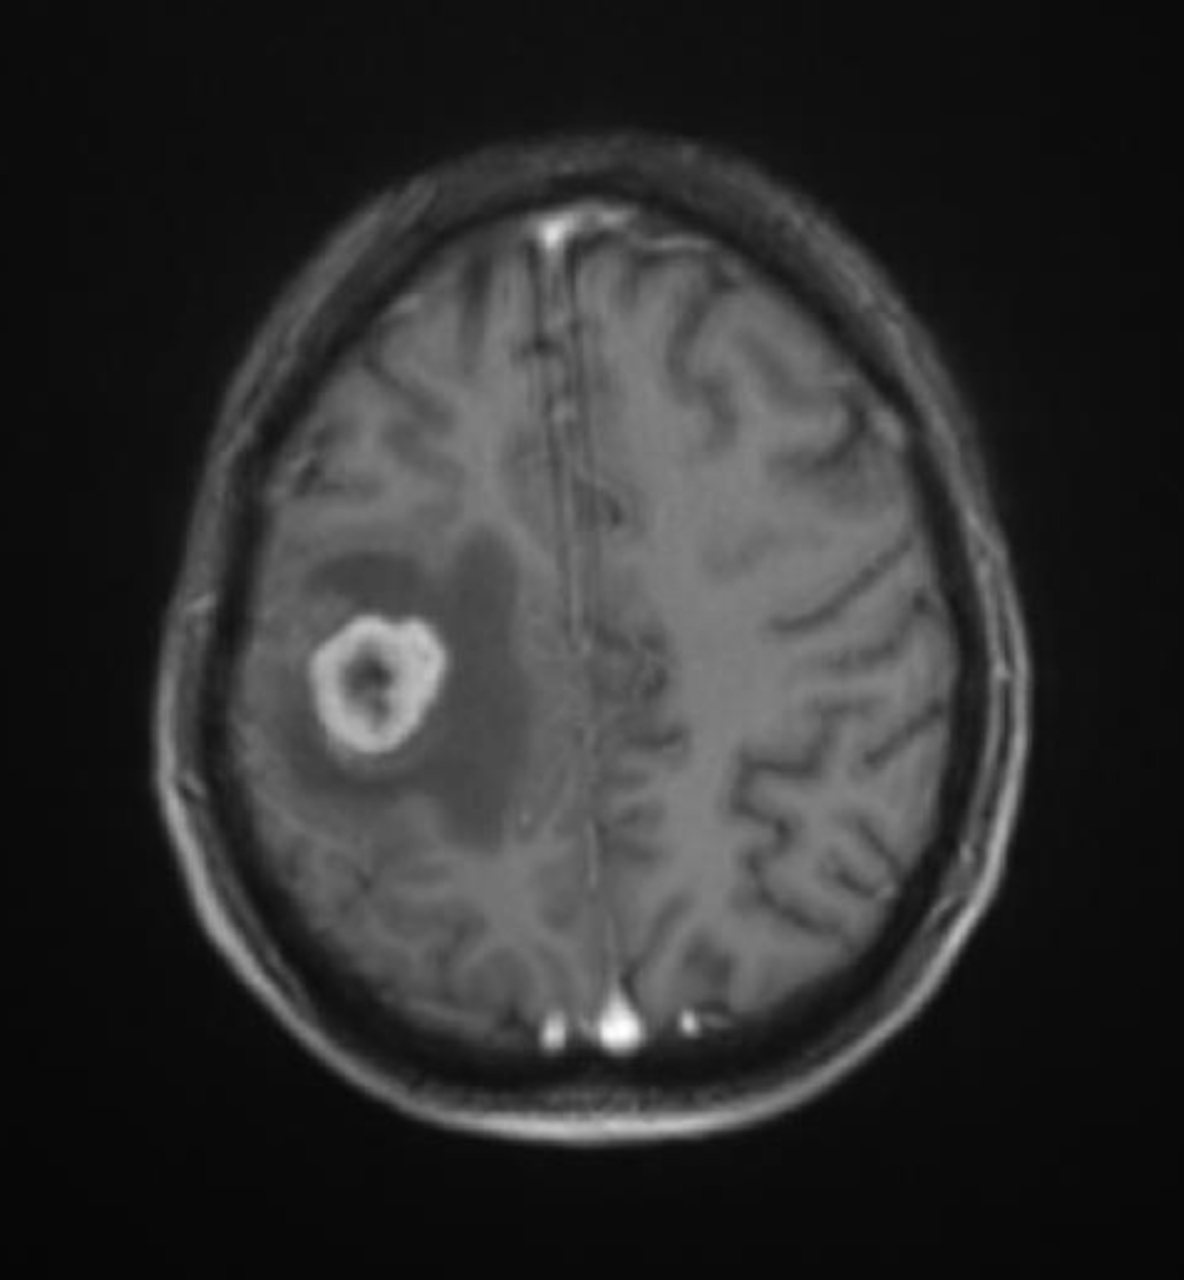

Vous avez fait réaliser l’examen suivant (fig. 1) :

Figure 1 (source : M. Roulleaux Dugage)

Le liquide céphalorachidien (LCR) étant blanc, il s’agit d’une IRM rachidienne pondérée en T2.

En effet, on voit bien ici la compression médullaire par une masse hétérogène du corps vertébral de T12. Celle-ci explique les douleurs neuropathiques + hypoesthésie T12, sans syndrome sous-lésionnel pour le moment.

Il existe une lésion hétérogène du corps vertébral de T12, non centrée sur un disque et fortement évocatrice de métastase rachidienne.

Pour rappel, on est ici devant un tableau de compression médullaire incomplet : – syndrome lésionnel (présent ici) : douleur ou déficit radiculaire ; – syndrome sous-lésionnel (non présent ici) : déficit sensitivomoteur, signe d’irritation pyramidale, troubles sphinctériens ; – syndrome rachidien (présent ici) : syndrome douloureux local.

Il n’existe pas d’hypotonie du sphincter anal. Vous avez hospitalisé la patiente, introduit une corticothérapie par voie intraveineuse (IV) et laissé la patiente en décubitus dorsal strict en attendant l’avis des neurochirurgiens. Devant l’absence de déficit moteur et le caractère incomplet du tableau de compression médullaire, ceux-ci ne retiennent pas l’indication d’une prise en charge neurochirurgicale en urgence. En revanche, l’image est très suspecte d’une localisation tumorale secondaire, et vous faites hospitaliser la patiente pour bilan après lui avoir expliqué vos craintes. Un nouvel avis neurochirurgical préconise, si le cancer est avéré, une radiothérapie rapide T11-T12-L1. Il s’agirait d’une radiothérapie de 30 Gy en 10 fractions de 3 Gy.